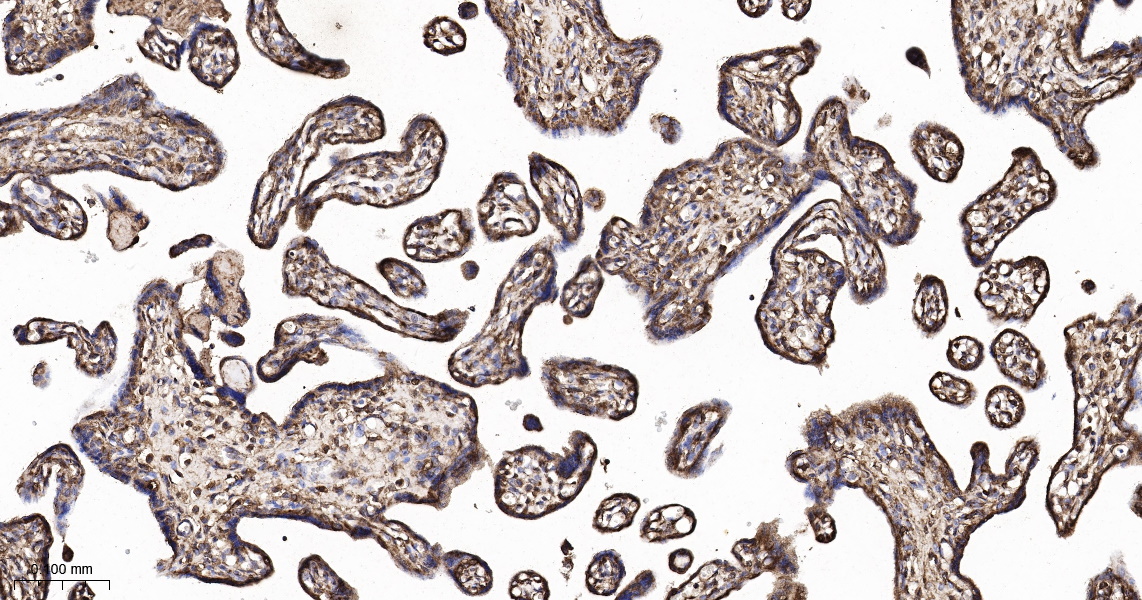

• IHC-P

IHC-P IHC-P1:100-500